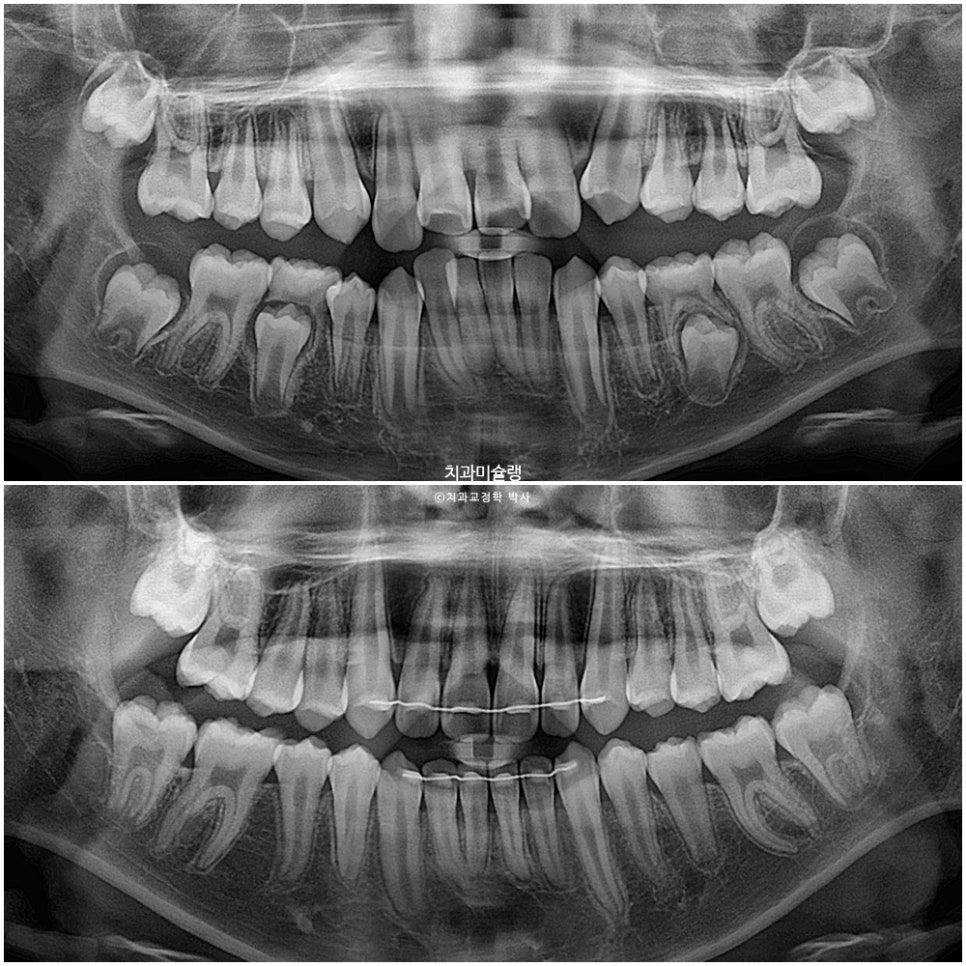

이제 전후비교 보겠습니다.

2023.07-2025.12

과개교합, 중심선의 개선.

앞니 돌출의 개선

2급 교합관계가 1급 교합관계로 개선되었습니다.

치근흡수는 없었으며 제2대구치가 잘 올라오는 중입니다.